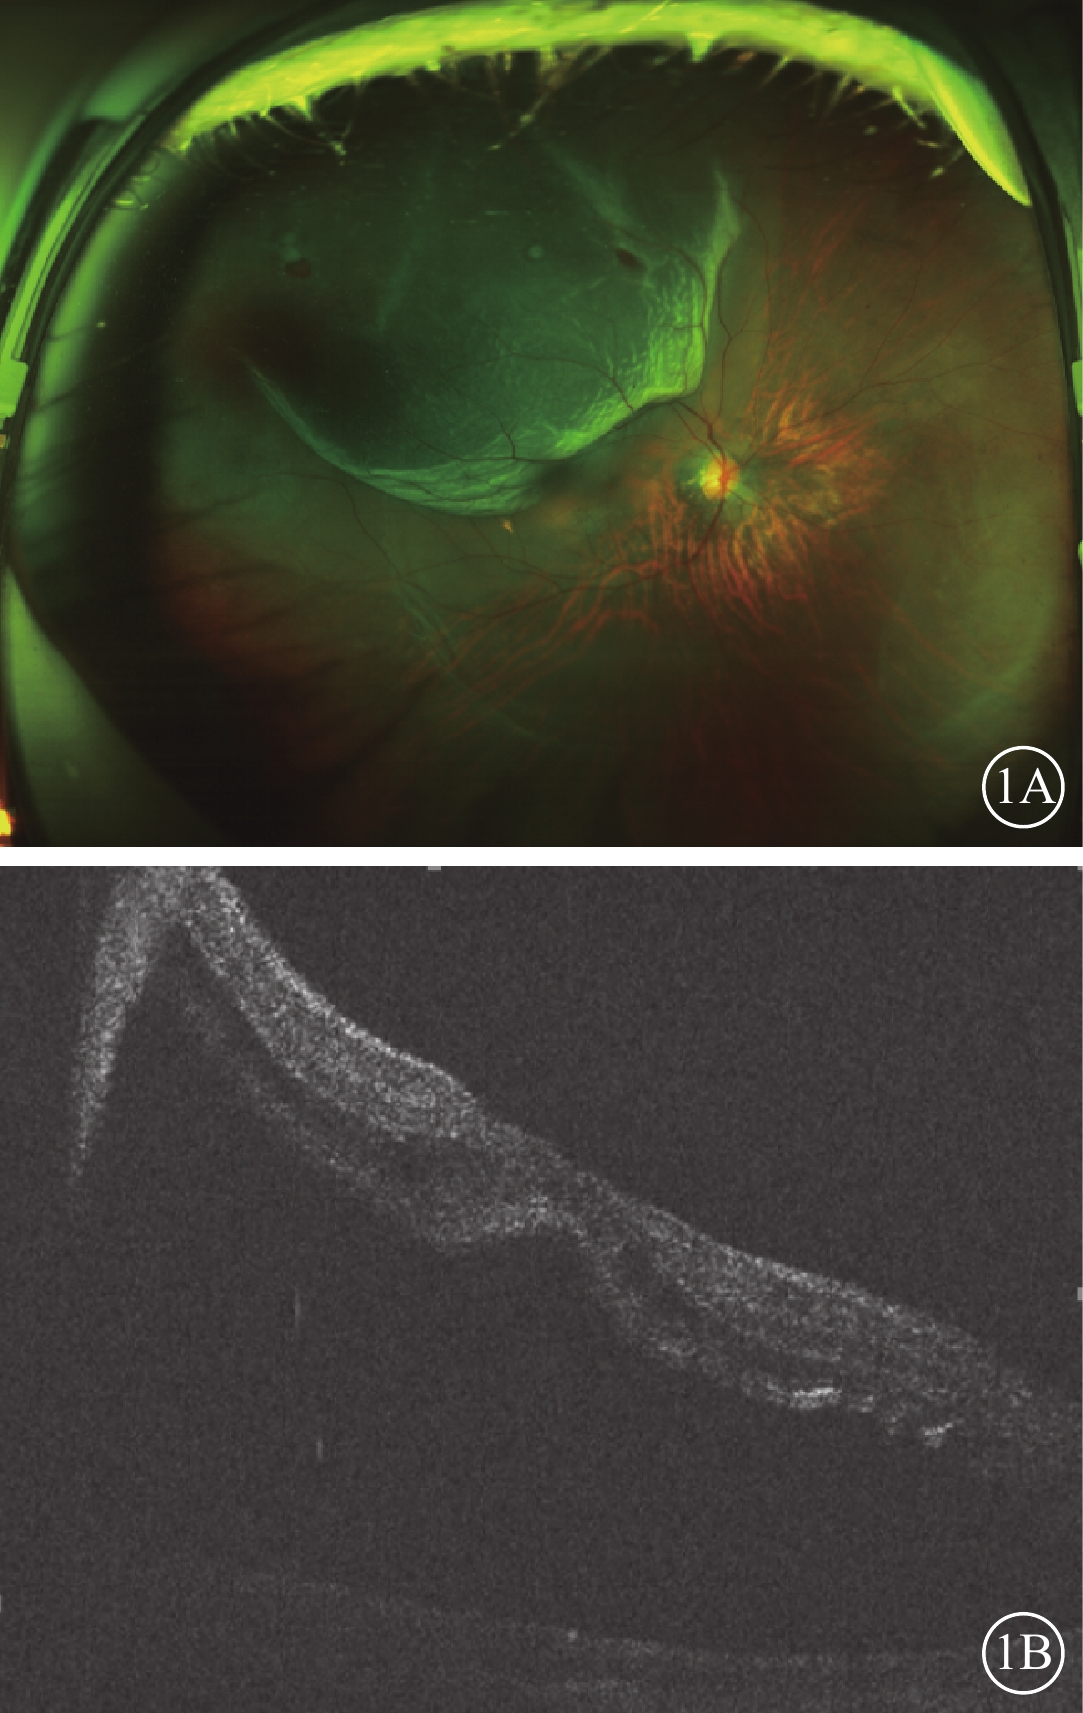

所有患眼行BCVA、眼壓、眼部B型超聲、雙目間接檢眼鏡、OCT及掃描激光檢眼鏡(SLO)檢查。12只眼中,BCVA<0.1、0.1~0.4、>0.4各4只眼(33.33%)。眼壓<10 mmHg(1 mmHg=0.133 kPa)4只眼(33.33%),10~15 mmHg 5只眼(41.67%),>15 mmHg 3只眼(25.00%)。視網膜脫離范圍累及1個象限(圖1A)3只眼(25.00%),累及2個象限7只眼(58.33%),累及3、4個象限各1只眼(8.33%)。視網膜脫離已累及黃斑(圖1B)8只眼(66.67%)。視網膜裂孔位于顳上方7只眼(58.33%),位于顳下方3只眼(25.00%),位于鼻上方2只眼(16.67%)。裂孔為小圓孔8只眼(66.67%),馬蹄樣裂孔3只眼(25.00%),不規則裂孔1只眼(8.33%)。PVR A級4只眼(33.33%),B級6只眼(50.00%),C1級2只眼(16.67%)。正視眼 2只眼(16.67%),近視眼10只眼(83.33%)。屈光度-3.00~-6.00 D 1只眼(8.33%);>-6.00 D 9只眼(75.00%)。

圖1

患眼手術前SLO及OCT像。1A示SLO像,可見右眼顳上方視網膜呈青灰色隆起,隆起區可見兩個小圓孔;1B示OCT像,可見黃斑區神經上皮脫離

圖1

患眼手術前SLO及OCT像。1A示SLO像,可見右眼顳上方視網膜呈青灰色隆起,隆起區可見兩個小圓孔;1B示OCT像,可見黃斑區神經上皮脫離

所有患眼行BCVA、眼壓、眼部B型超聲、雙目間接檢眼鏡、OCT及掃描激光檢眼鏡(SLO)檢查。12只眼中,BCVA<0.1、0.1~0.4、>0.4各4只眼(33.33%)。眼壓<10 mmHg(1 mmHg=0.133 kPa)4只眼(33.33%),10~15 mmHg 5只眼(41.67%),>15 mmHg 3只眼(25.00%)。視網膜脫離范圍累及1個象限(圖1A)3只眼(25.00%),累及2個象限7只眼(58.33%),累及3、4個象限各1只眼(8.33%)。視網膜脫離已累及黃斑(圖1B)8只眼(66.67%)。視網膜裂孔位于顳上方7只眼(58.33%),位于顳下方3只眼(25.00%),位于鼻上方2只眼(16.67%)。裂孔為小圓孔8只眼(66.67%),馬蹄樣裂孔3只眼(25.00%),不規則裂孔1只眼(8.33%)。PVR A級4只眼(33.33%),B級6只眼(50.00%),C1級2只眼(16.67%)。正視眼 2只眼(16.67%),近視眼10只眼(83.33%)。屈光度-3.00~-6.00 D 1只眼(8.33%);>-6.00 D 9只眼(75.00%)。

圖1

患眼手術前SLO及OCT像。1A示SLO像,可見右眼顳上方視網膜呈青灰色隆起,隆起區可見兩個小圓孔;1B示OCT像,可見黃斑區神經上皮脫離

圖1

患眼手術前SLO及OCT像。1A示SLO像,可見右眼顳上方視網膜呈青灰色隆起,隆起區可見兩個小圓孔;1B示OCT像,可見黃斑區神經上皮脫離